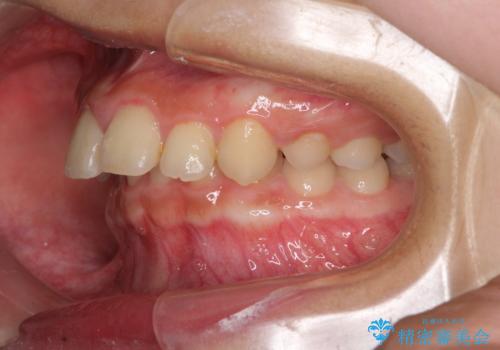

飛び出した前歯をインビザラインですっきりと

- 深い咬み合わせと上顎前歯の突出感を気にして来院された患者様です。

当院では通常、臼歯の咬合が理想的な位置に対して上顎が前方位にある場合。ワイヤー矯正または補助装置の併用したインビザライン矯正を選択しています。

今回は、できるところまででいいのでインビザライン単体で治療をしたいという希望があったため、インビザラインにて矯正治療を行うこととしました。

正面や横からの写真ではきれいに治っており、患者様は大変満足のいく仕上がりとなりましたが、深い咬み合わせの改善は不十分で、奥歯の咬み合わせも改善させることができませんでした。

インビザラインは、咬合力の強い方ですと、奥歯が歯肉内にめり込んでしまうため、前歯が強く接触してしまうことがあります。

こちらの方は、奥歯はしっかりと噛んだのですが、歯肉にめり込んでしまったことで、歯肉が腫れやすくなってしまいました。